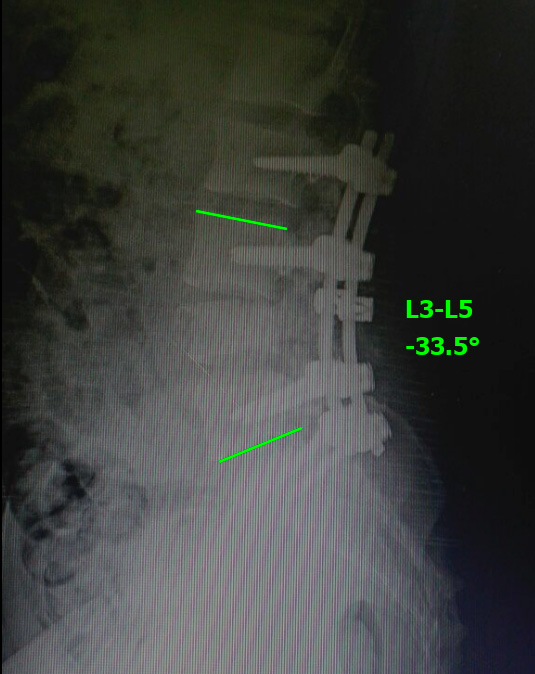

Se decide efectuar una cirugía con abordaje posterior lumbosacro, descompresión posterolateral directa por técnica de tipo eggshell, con resección del arco posterior de L4 y reducción de los fragmentos en retropulsión.25-27 Se realiza artrodesis lumbosacra larga L2-S1 (Figuras 4 y 5).

Figura 4.

Caso 1. Control radiográfico posoperatorio (perfil).

El paciente evoluciona favorablemente con cicatrización de la herida quirúrgica. Comienza con rehabilitación en el posoperatorio inmediato. Se corrige la cifosis segmentaria con medición radiográfica a los seis meses de la cirugía adecuada (Cobb L3-L5 33°, lordosis lumbar 44°, incidencia pelviana 44°, IP-LL 0°, inclinación de la pelvis 18°). El paciente recupera la sensibilidad por completo y evoluciona con una secuela deficitaria parcial motora de raíz L4 izquierda, extensión activa del pie grado 3 (vence gravedad). La TC de control a los dos años muestra la consolidación (Figura 6). Vuelve a montar a caballo (Figura 7 y video).